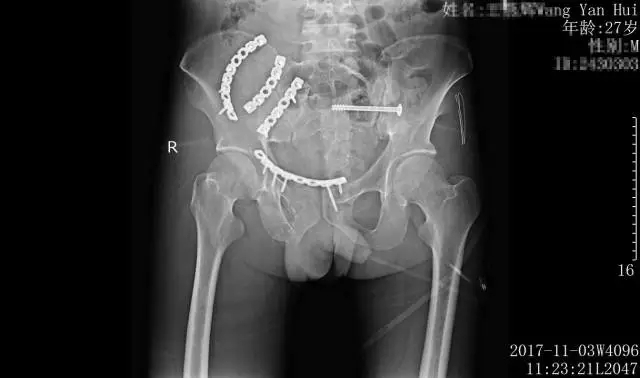

术后影像检查,骨盆骨折端完全吻合

骨盆多发骨折考虑骨盆前、后环均为不稳定,既有前后暴力损伤,也有垂直暴力损伤,手术指证明确。医生经综合考虑,决定以控制再次损伤为主,采用左侧骶髂关节行闭合空心螺钉固定,右侧髂骨翼及耻骨上支骨折行腹直肌外侧入路行骨折固定,以一个小切口解决大半骨盆环的复位固定。

手术如期进行,在黄东永医学团队的共同努力下,骨盆骨折骶髂螺钉内固定及腹直肌外侧入路处理复杂骨盆骨折手术顺利完成,标志着惠州三院骨科医学中心对复杂骨盆骨折微创手术又迈进了一大步。

术后,患者生命体征平稳,无副损伤出现。一期骨盆骨折手术后1周,患者再次进行了二期四肢骨折重建手术,术后病情稳定,获得了良好的治疗效果,目前正在积极的康复当中。